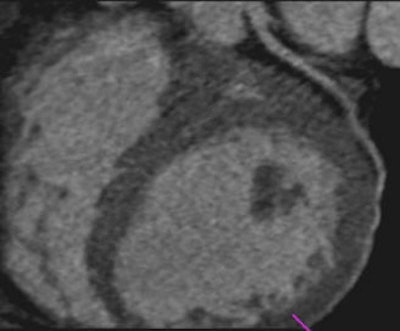

Images of a 65-year-old male patient acquired in dual-source CT high-pitch mode show good enhancement of the coronary arteries down to their distal portions. Top image shows calcified stenosis at the origin of the proximal portion of the left anterior descending (LAD) artery.Bottom image depicts the left circumflex (LCX) artery, and an absence of atherosclerotic lesions. The acquisition consisted of a whole-chest CT angiography exam obtained without beta blockers or electrocardiac gating. All images courtesy of Dr. Martine Rémy-Jardin.Collimation was set thin at 0.6 mm, and protocols for both machines used individually adapted selection of kVp for tubes A and B, at 100 kVp (body weight < 80 kg) or 120 kVp (body weight 80-120 kg). Automatic adjustment was achieved using CareDose (Siemens) with a reference setting of 90 mAs.